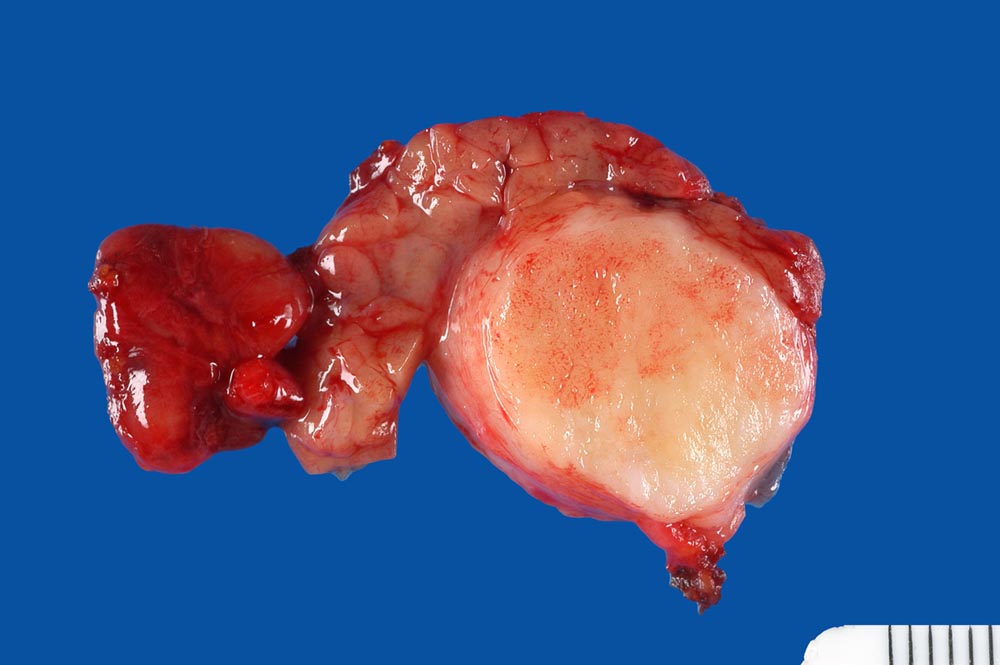

Makroskopie:

Makroskopisch sind pleomorphe Adenome scharf begrenzt. In den grossen Speicheldrüsen sind die meist solitär wachsenden Knoten von einer Kapsel umgeben, nicht aber in den kleinen Speicheldrüsen. Rezidivtumoren bilden oftmals multiple Knoten.

• Scharf begrenzter bekapselter Tumor bestehend aus epithelialen, myoepithelialen und mesenchymalen Anteilen.

• Oben im Präparat dem Tumor kappenförmig aufsitzende seromuköse Speicheldrüse (Glandula submandibularis). Das sollte der Kliniker dem Pathologen mitteilen: